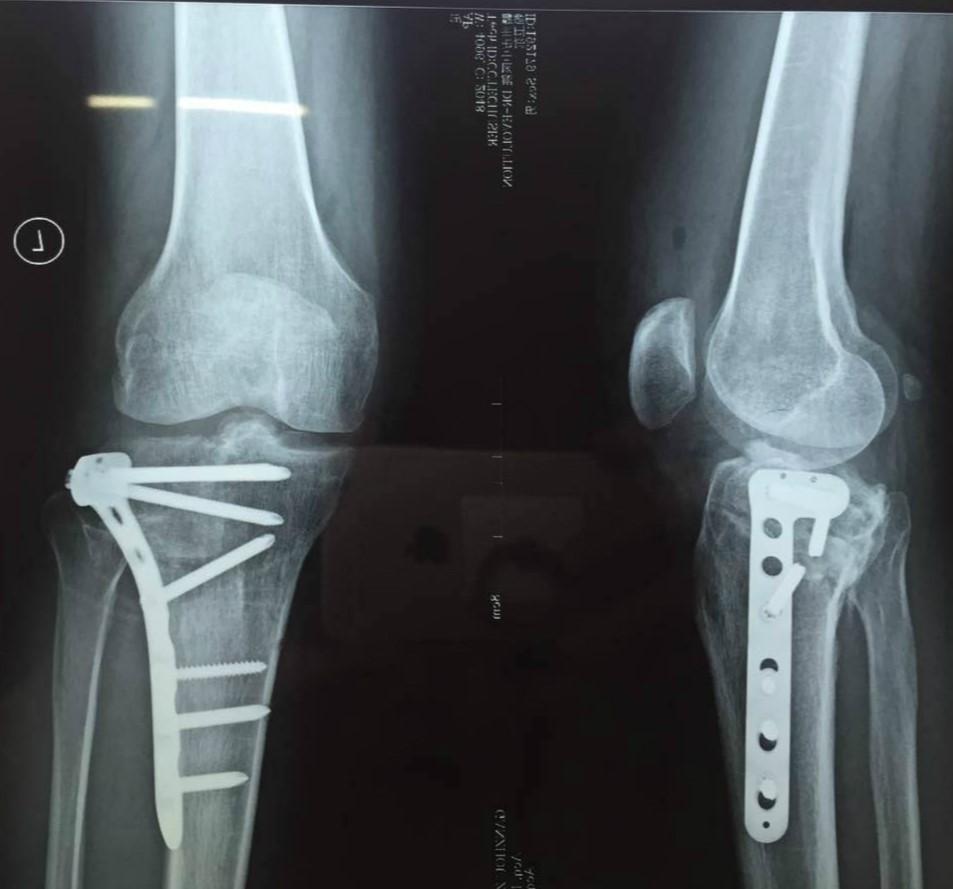

男性病人,43歲,左脛骨平臺后外側塌陷骨折。

有了完美的術前規(guī)劃,那完美的術后效果也就不是奢望。